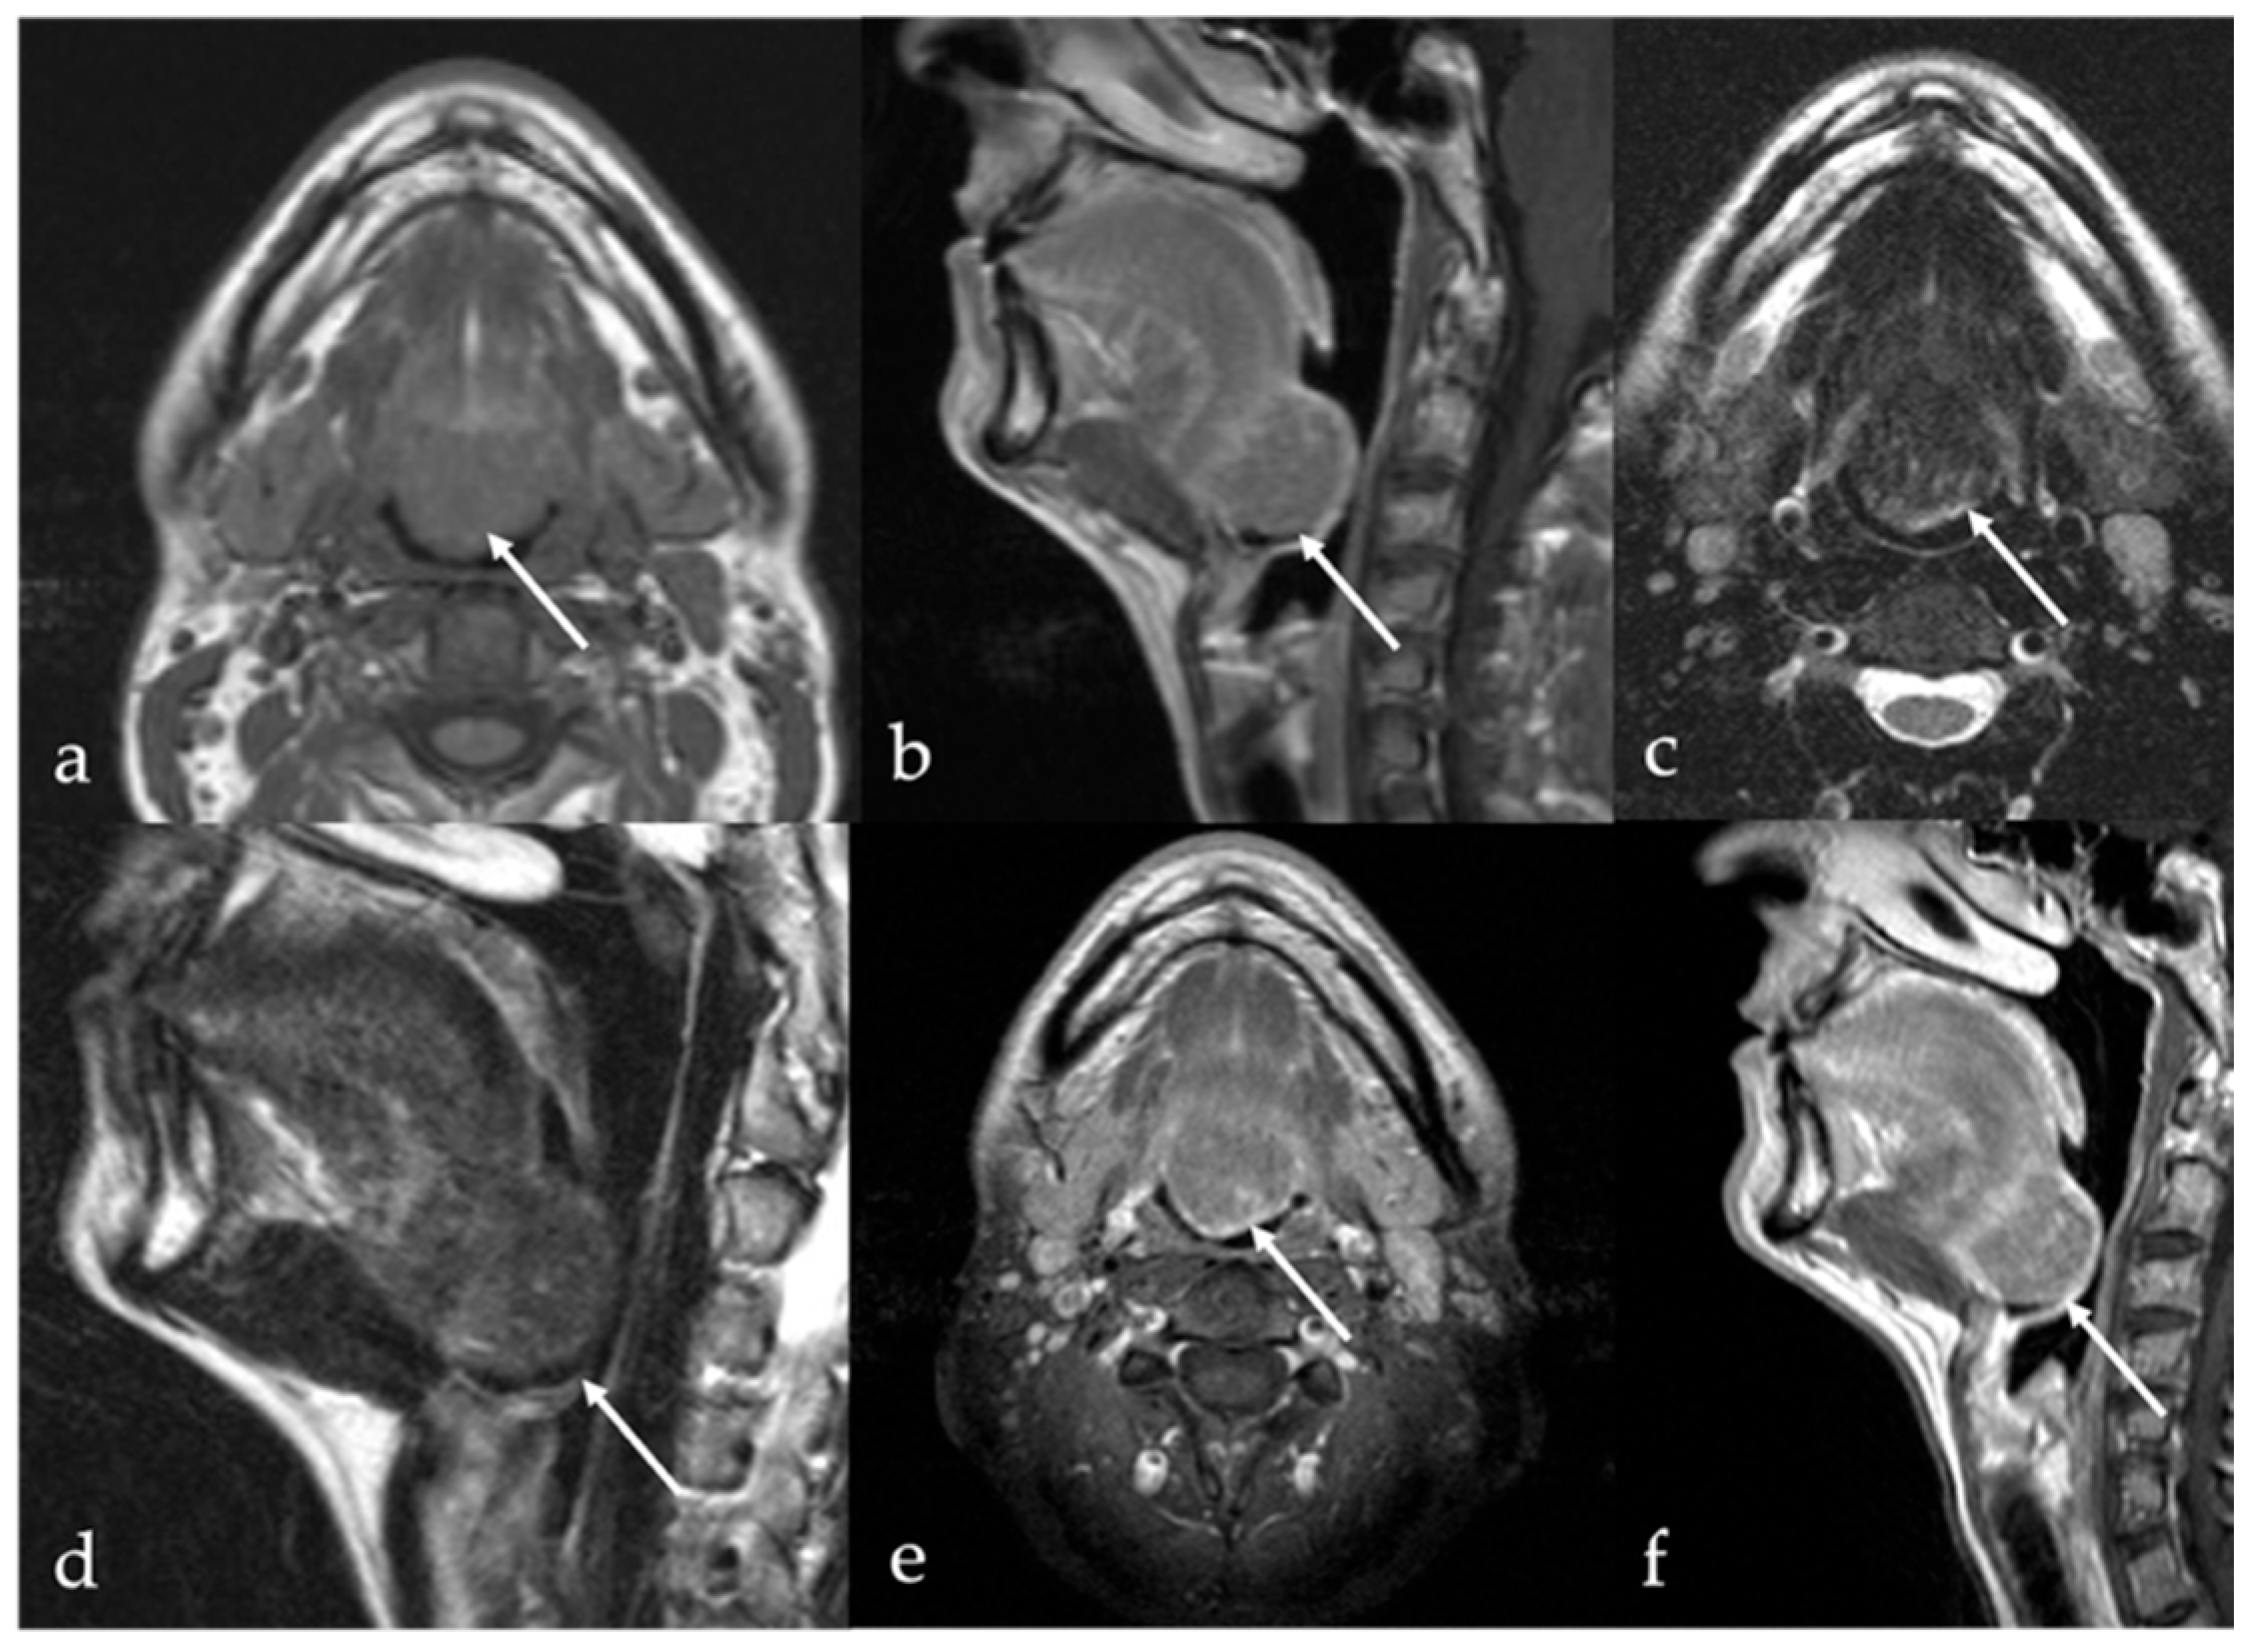

6. Dermoid Cysts

7. Thyroglossal Duct Remnants

7.1. Thyroglossal Duct Cyst

| Dermoid cyst [1,13,14] | CT: free fat and calcified corpuscles (“sack of marbles” sign) | Vascular malformation, epidermoid cysts, lipoma |

| Epidermoid cyst [14] | MRI: high SI on DWI, and restricted diffusion with low values on ADC map | Vascular malformation, dermoid cysts |

| Thyroglossal duct cyst [15] Ectopic thyroid tissue [16] | Cyst Same features as thyroid tissue | Lingual tonsil mucous retention cyst Squamous cell carcinoma and lymphoma of the tongue base |